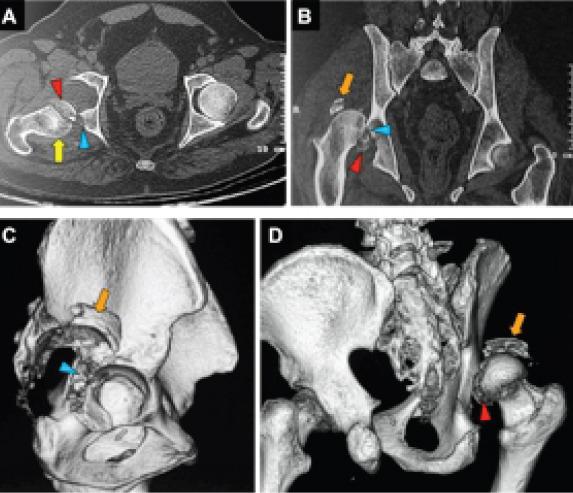

In this case report, we present a neglected 15 days old rare injury (Pipkin type IV femoral head fracture) in a 60 years old male patient that was given a trial of hip preservation surgery by ORIF through posterior (Kocher-Langenbeck) approach.

在本病例报告中,我们呈现了一名60岁男性患者,其15天前的罕见损伤(Pipkin IV型股骨头骨折)被忽视,通过后入路(Kocher-Langenbeck)进行切开复位内固定,尝试保髋手术。